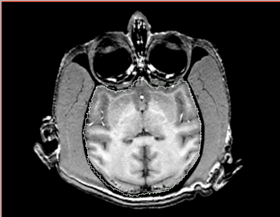

* Correction of the bias in vervet MRI. Acquisition parameters: 3T GE scanner, single-channel dedicated RF coil (Litzcage, Doty Scientific, Columbia, SC); 3D SPGR sequence (TI 600ms, TE 3.276ms, TR 15.28ms; flip angle 15 deg; matrix 256x256; FOV 12cm; in-plane resolution 0.47 mm; slice thickness 0.5 mm). | * Correction of the bias in vervet MRI. Acquisition parameters: 3T GE scanner, single-channel dedicated RF coil (Litzcage, Doty Scientific, Columbia, SC); 3D SPGR sequence (TI 600ms, TE 3.276ms, TR 15.28ms; flip angle 15 deg; matrix 256x256; FOV 12cm; in-plane resolution 0.47 mm; slice thickness 0.5 mm). | ||

- Correction of the bias in vervet MRI. Acquisition parameters: 3T GE scanner, single-channel dedicated RF coil (Litzcage, Doty Scientific, Columbia, SC); 3D SPGR sequence (TI 600ms, TE 3.276ms, TR 15.28ms; flip angle 15 deg; matrix 256x256; FOV 12cm; in-plane resolution 0.47 mm; slice thickness 0.5 mm).